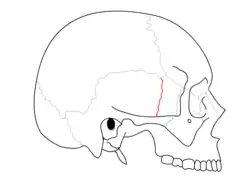

Trauma

Temporal bone fractures were historically divided into three main categories, longitudinal, in which the vertical axis of the fracture paralleled the petrous ridge, horizontal, in which the axis of the fracture was perpendicular to the petrous ridge, and oblique, a mixed type with both longitudinal and horizontal components. Horizontal fractures were thought to be associated with injuries to the facial nerve, and longitudinal with injuries to the middle ear ossicles.[6] More recently, delineation based on disruption of the otic capsule has been found as more reliable in predicting complications such as facial nerve injury, sensorineural hearing loss, intracerebral hemorrhage, and cerebrospinal fluid otorrhea.[7]